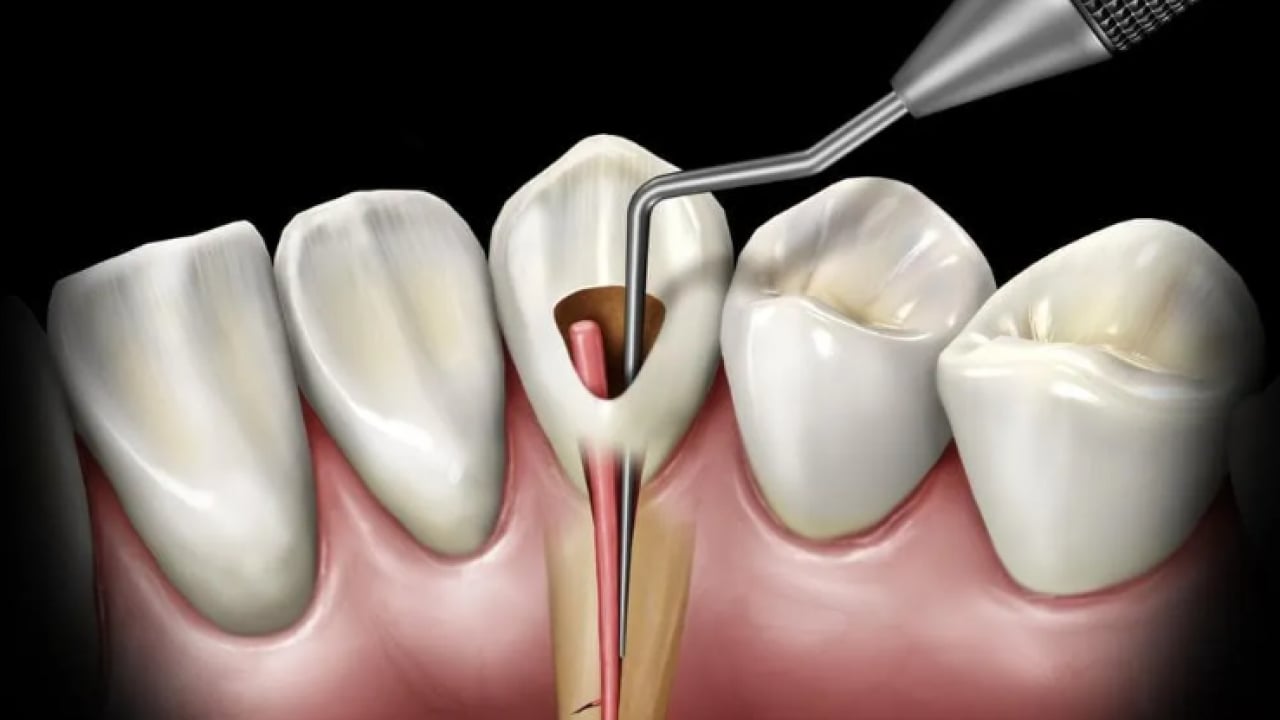

Dr. Öğr. Üyesi Sezer, "Dişin kök kanallarındaki sinir ve damar dokusu temizlenir, kanal duvarları arındırılır ve uygun materyallerle doldurularak diş restore edilir. Geçmeyen zonklayıcı ağrılar, gece uykudan uyandıran şiddetli ağrı, yüzde şişlik oluşturan apse, yemek yerken sıcakla veya dişe bastırınca oluşan hassasiyet gibi durumlar kanal tedavisi gerekliliğini düşündürür" diye konuştu.

“TEDAVİ YAPILMAZSA DOKU HASARINA YOL AÇABİLİR” Kanal tedavisi yapılmazsa dişte veya vücutta hangi sorunlar görülebileceğine değinen Dr. Öğr. Üyesi Sezer, "Kanal tedavisi yapılmadığında kök ucunda oluşan lezyonlar büyüyerek kistleşebilir, büyük kemik kayıplarına ve doku hasarına yol açabilir. Dişte sürekli hassasiyet ve spontan ağrılar oluşabilir. Kronikleşmiş enfeksiyonlar bazen akut şekilde ani yüz şişliklerine dönüşebilir yahut ağrı vermese bile zaman içinde ilerleyebilir. Ağız içindeki bu enfeksiyon odakları diyabet, kalp hastalıkları gibi sistemik durumları kötü etkileyebilir. Dişlerin tedavi edilmeyip durumları kötüleştiğinde çekilmek zorunda kalınması, çiğneme fonksiyonunda bozulmaları ve bununla beraber bağışıklık sisteminin zayıflamasını da beraberinde getirir" dedi.